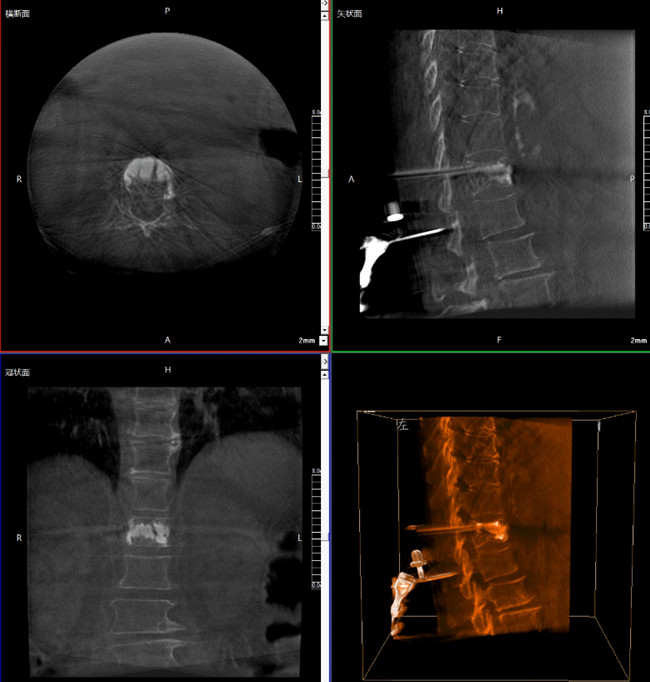

步驟一:C形臂三維重建+機器人手術(shù)規(guī)劃

使用普愛醫(yī)療三維C形臂對患者進行胸椎影像掃描及三維重建,圖像被同步傳輸?shù)狡諓坩t(yī)療骨科機器人導(dǎo)航系統(tǒng)。

C形臂三維重建+骨科機器人手術(shù)規(guī)劃

借助骨科機器人的規(guī)劃軟件進行術(shù)前手術(shù)路徑模擬規(guī)劃,找到穿刺位置和角度,操作機械臂快速完成手術(shù)入點的準確定位。

*術(shù)前規(guī)劃